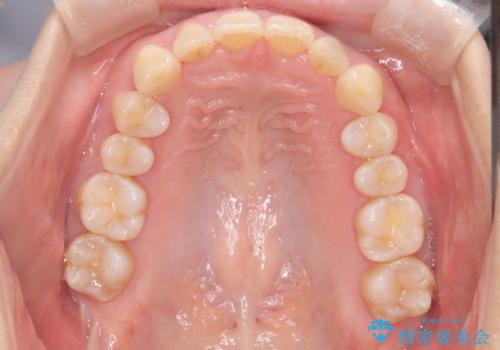

- 前歯が出ていることを主訴に来院されました。

インビザラインにて臼歯部の遠心移動及びIPRを行なっています。

叢生量が多いケースでしたが、綺麗な歯並びとなり患者様にも満足していただきました。

非抜歯矯正のため口元の変化はありません。